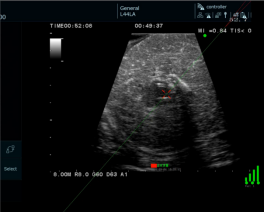

近日,云南省第一人民医院肝胆胰外科主任晋云带领团队成功实施了“磁导航技术引导下的腹腔镜肝脏肿瘤微波消融手术”。较目前常见术中导航系统而言,这一技术能更精准选择肿瘤穿刺位置,规划穿刺路径及评估路径安全,减少反复无效穿刺带来的肝损伤,更有效引导腹腔镜肝脏消融手术,确保了消融的成功率和安全性。

此次接受手术的患者患有肝脏肿瘤,传统消融方式如同“盲打”,需凭借医生经验反复穿刺调整,才能将消融针精确送达目标位置,不仅手术时间长、创伤大,也增加了并发症风险。而团队此次采用的 “磁导航腹腔镜微波消融”新技术,则完美解决了这一临床痛点。

晋云表示,该技术犹如为手术医生安装了“精准的GPS实时导航系统”。手术中,通过磁导航系统,虚拟的穿刺路径清晰明了,并且借助该技术,还能虚拟出能量释放点,精度达到毫米级。医生可藉此提前规划出更加适合患者的手术路径,操控消融针在导航系统的引导下,一次性精准抵达病灶核心,实现了“指哪打哪”的毫米级精准消融,彻底避免了传统方式的反复穿刺。

电磁导航毫米级靶向精准穿刺